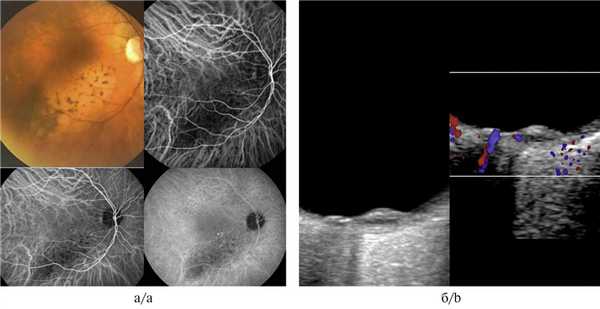

Примеры ангиографии с флюоресцеином и индоцианином зеленым при гемангиоме хориоидеи с четкими контурами

Гемангиома хориоидеи характеризовалась выраженными отличительными признаками как при проведении ангиографии с индоцианином зеленым, так и при УЗИ с ЦДК. Данную патологию отличали идентификация патогномоничных сосудистых паттернов в виде рисунка «рыбацкой сети», сети в виде «кружева» и гиперфлюоресценция на всех фазах исследования (рис. 5, а, б). При проведении УЗДГ выявлялся высокоскоростной и среднерезистентный кровоток (рис. 5, в).

Рис. 5. Гемангиома хориоидеи при ангиографии с индоцианином зеленым.

а, б — сосудистые паттерны в виде рисунка «рыбацкой сети», сети в виде «кружева» и гиперфлюоресценция на всех фазах исследования; в — УЗДГ-картина: высокоскоростной и среднерезистентный кровоток в ткани опухоли (размер образования 1,8×9,2 мм).